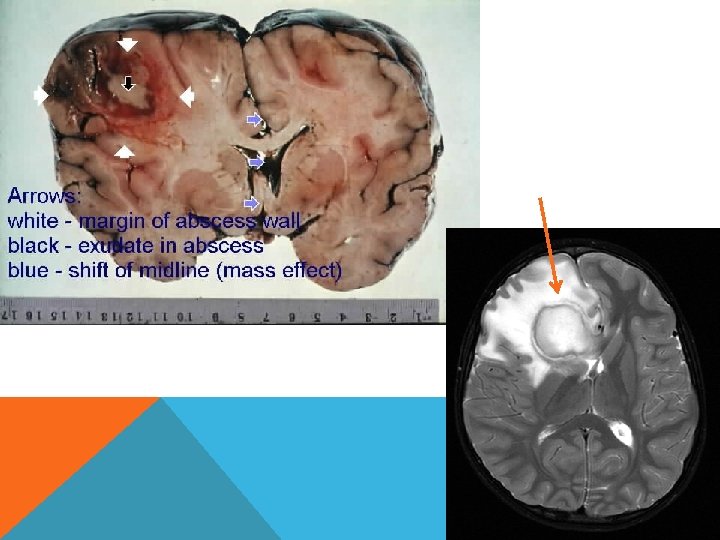

Абсцесс мозга Этиология. Пути проникновения инфекции: 1) путем контактного распространения (при гнойных заболеваниях среднего уха или околоносовых пазух – отиты, мастоидиты); 2) гематогенным путем; 3) через патологическое сообщение между полостью черепа и внешней средой (при проникающей ЧМТ, нейрохирургических манипуляциях, врожденных ликворных свищах).

Абсцесс Мозга

Патогенез Рост микроорганизмов. Локализованный энцефалит (церебрит) с отеком мозга. Гнойное расплавление очага Формирование капсулы. Клиническая картина Общеинфекционные симптомы (недомогание, лихорадка, тахикардия и т. д. ) Внутричерепная гипертензия Очаговые неврологические симптомы в зависимости от локализации абсцесса (эпилептические припадки, парезы, гемианопсия, афазии, мозжечковая симптоматика)

Диагностика Люмбальную пункцию не проводить! ОАК - лейкоцитоз и ускорение СОЭ. Рентгенография - наличие газа в полости черепа КТ абсцесс выглядит как зона низкой плотности с масс-эффектом. При введении конираста вокруг гиподенсивного центра выявляется тонкая кольцевидная гиперденсивная зона с ровными контурами. МРТ, абсцесс выглядит как относительно гомогенная гиперинтенсивная зона, имеющая слоистую структуру.